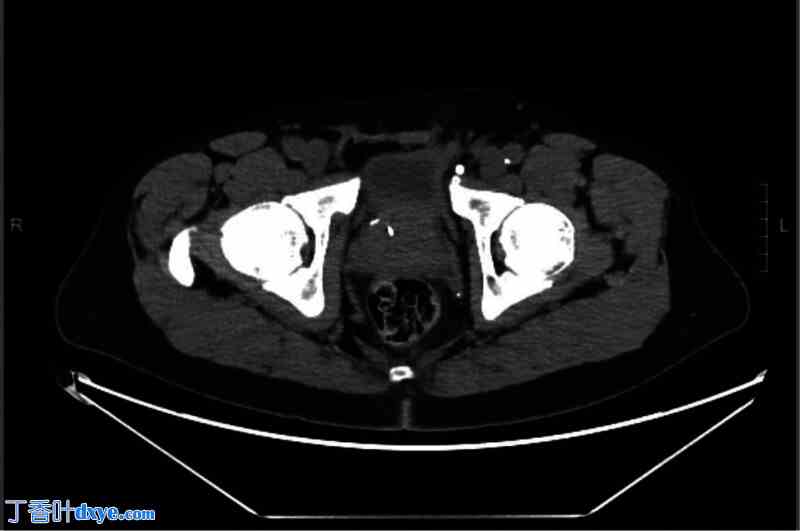

一名50岁男性患者,左侧腹股沟处有一可复位肿块。体格检查符合腹股沟疝的诊断。经腹腔镜腹膜前入路(TAPP)探查术中,未在直间隙或间接间隙发现疝。术前体格检查发现的肿块被认为是精索脂肪瘤。切开腹膜后,腹腔镜下切除精索脂肪瘤,并植入补片。术后第4天,患者联系外科医生报告疝“复发”。CT扫描(图3)显示膀胱经腹膜外间隙突出至网片修补处内侧。

图3

这张盆腔CT扫描图显示左侧腹膜外间隙疝,膀胱内充满疝内容物,疝内容物位于先前放置的经腹膜前入路腹腔镜疝修补网片内侧。耻骨结节附近可见一枚手术钉,标记网片的内侧边缘。